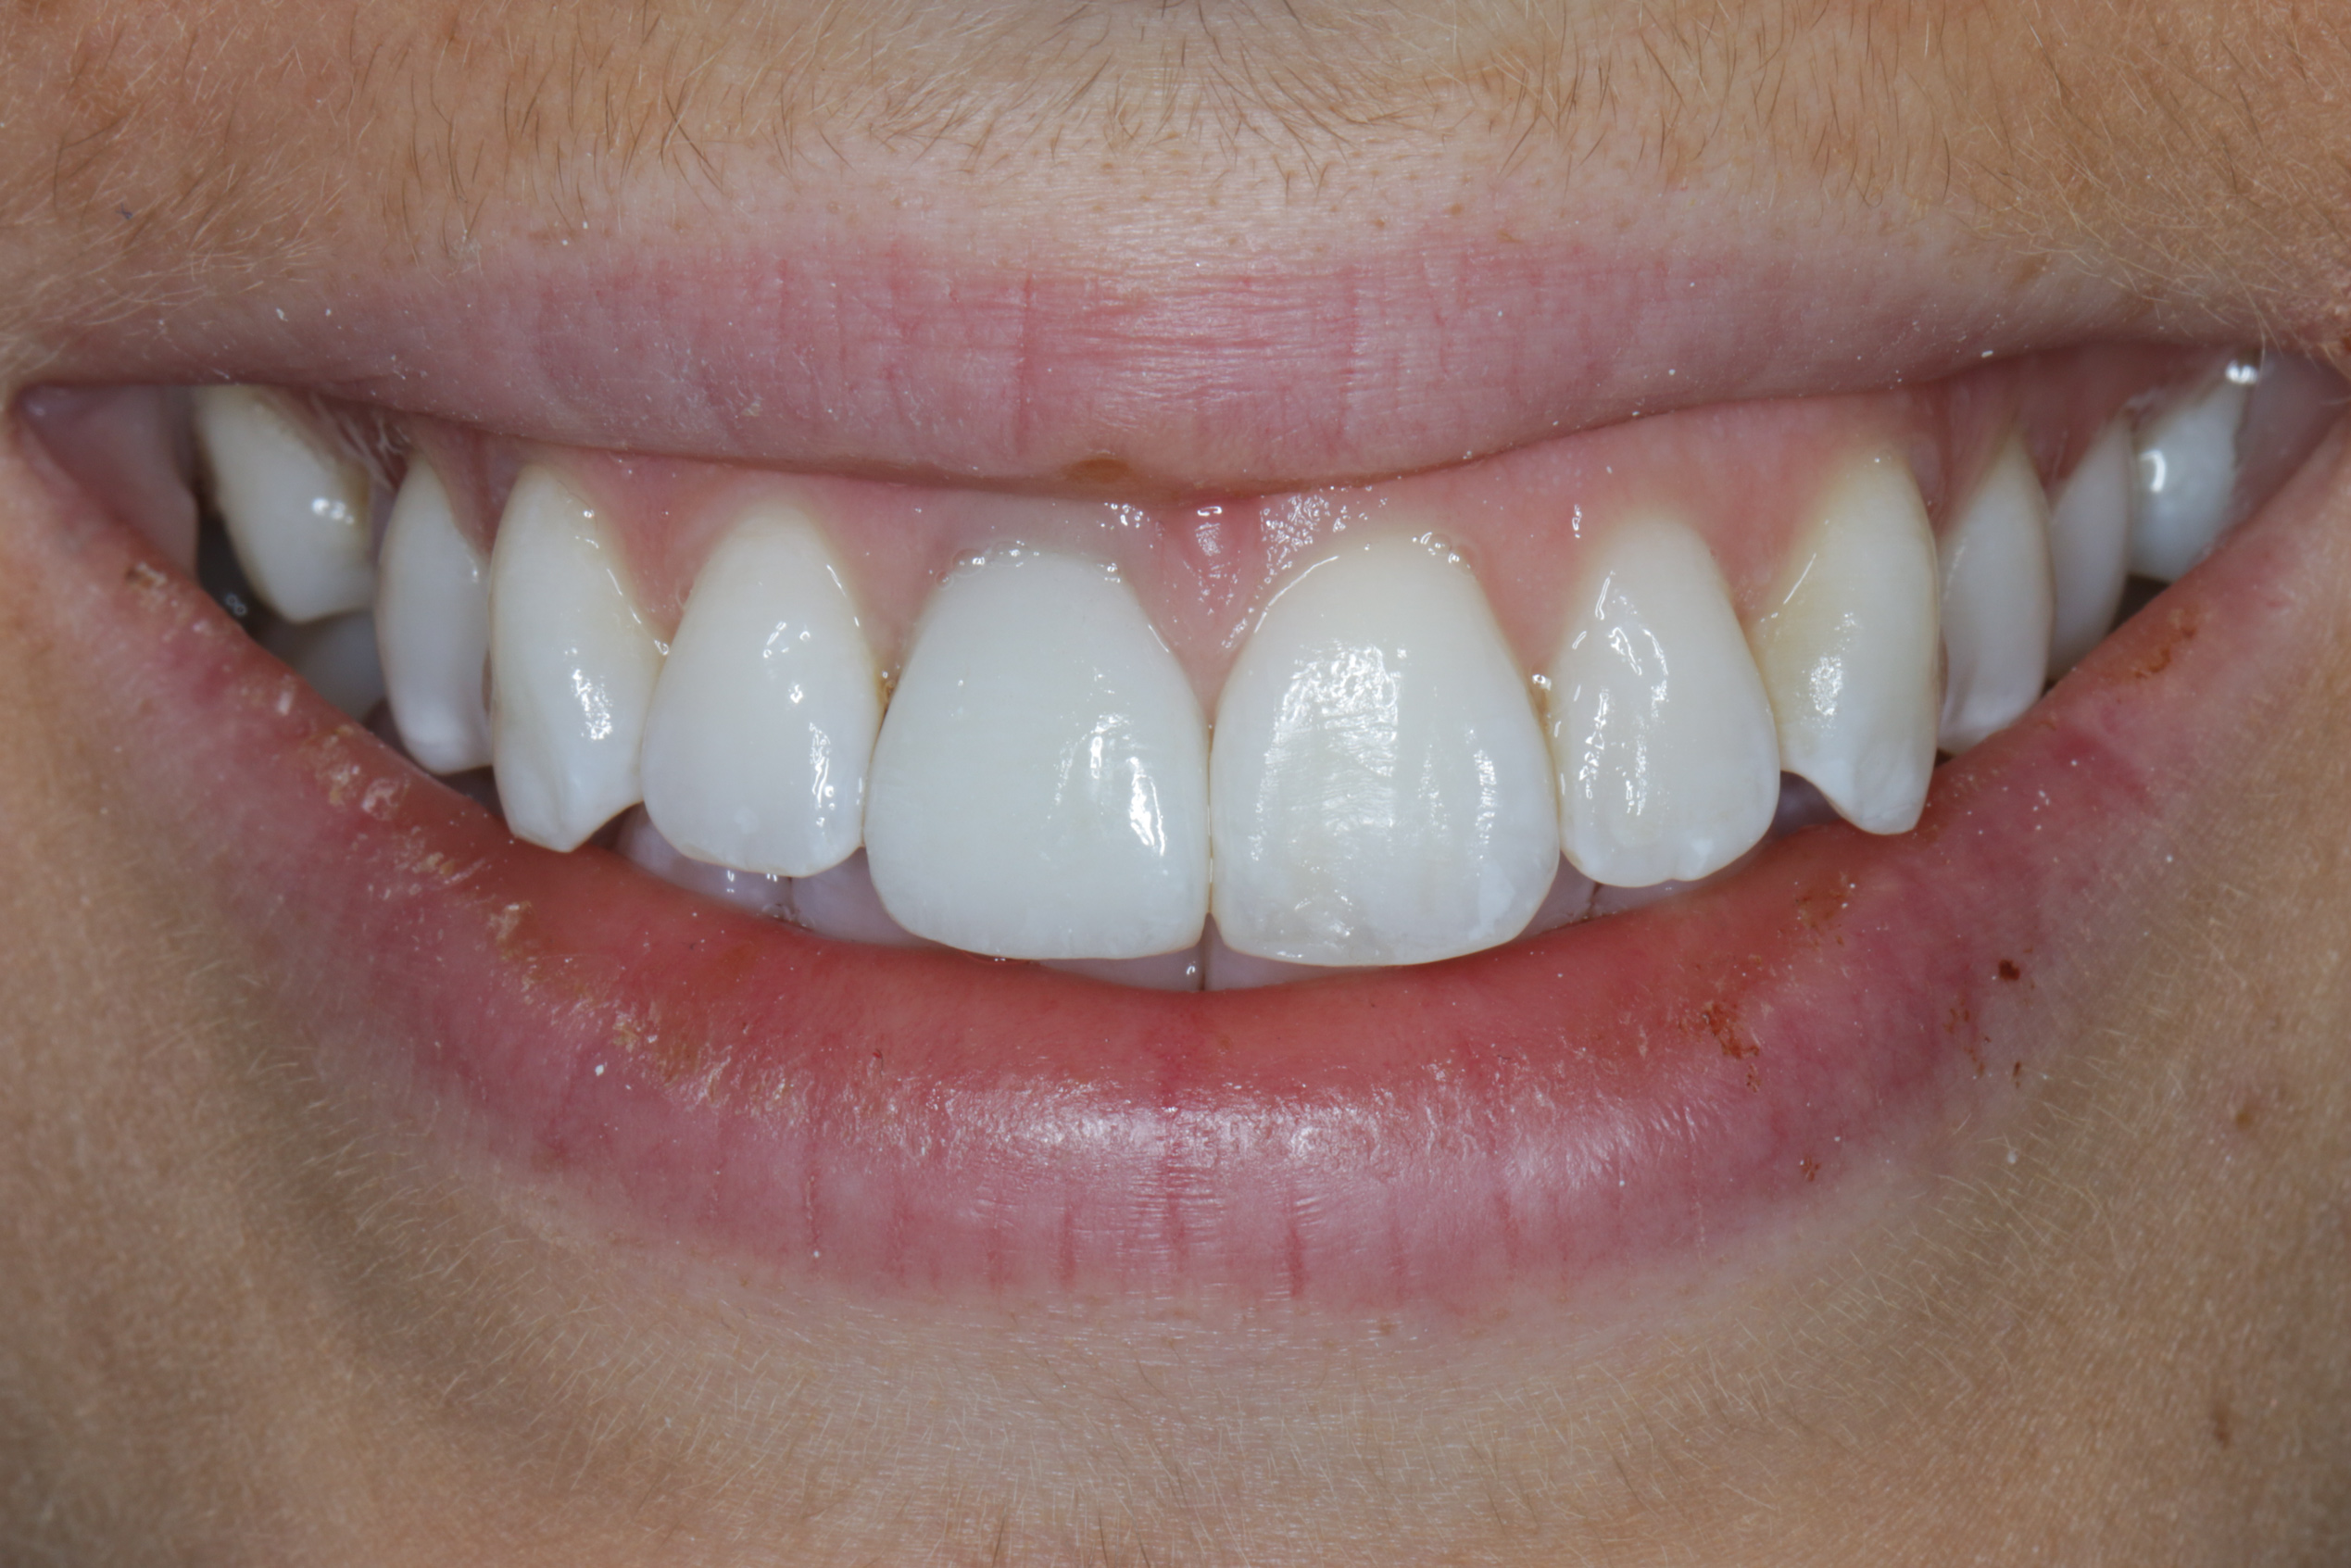

Fig 12. Immediate insertion of provisional restoration.

Figure 12